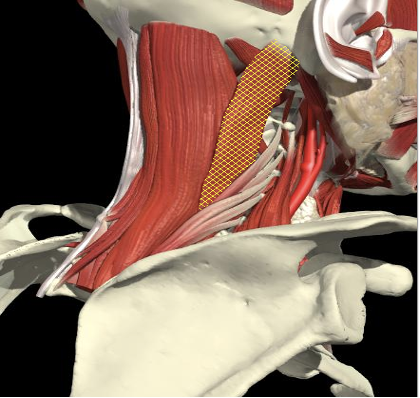

Structures to Avoid

Nerves in Posterior Triangle

Accessory nerve

Lies on LS, enters 1cm cranial to EP posterior border of SCM and runs on line to between middle and lower third of trapezius.

Should inject splenius and levator over 1cm above EP

Cervical plexus cutaneous branches

Mid point of posterior border

Inject levator above this point

Landmarks

Cervical plexus

Midpoint of SCM (EP)

Middle and lower third of Trapezius